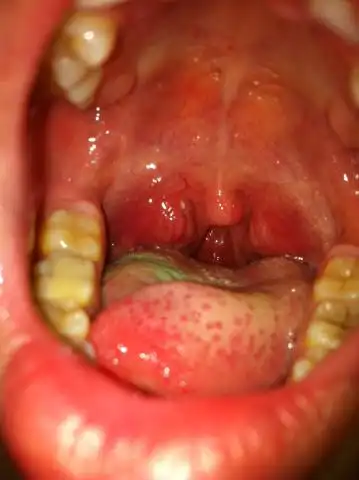

疱疹性咽峡炎

主要症状: 高热,嗓子痛,食欲差,口腔及咽喉出现灰白疱疹.